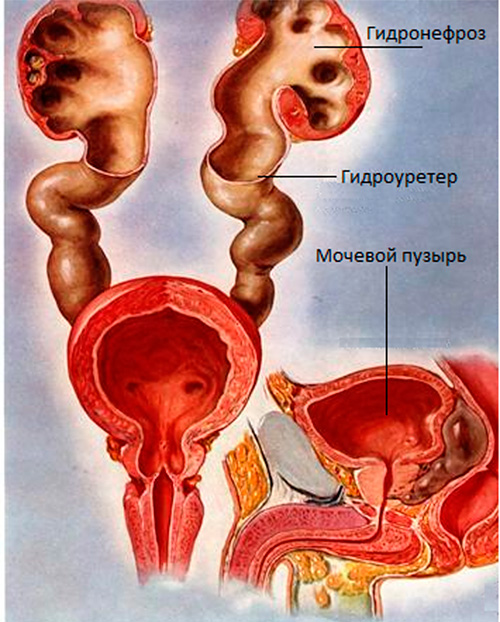

Рефлюксирующий мегауретер: Визуализация и медицинские изображения